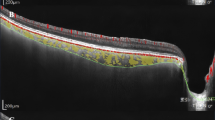

All 16 patients with FCE had unilateral involvement. The mean age of diagnosis was 52.56±14.00. The mean greatest linear dimension (GLD) of FCE was 636.25±265.11 μm. The mean choroidal thickness was 183.63±52.39 μm. Fourteen FCEs (87.5%) were conforming and two were non-conforming (12.5%). In the eyes with FCE, concurrent macular pathology was present in four cases (25.0%). Tractional pathologies of macular pucker and macular scar corresponded to the two non-conforming FCEs in the series. Polypoidal choroidal vasculopathy (PCV) and lacquer crack had a close topographic relationship with the FCE. The mean GLD was significantly larger in eyes with concurrent macular pathology than those without (878.00 vs 555.67 μm, P=0.029). In the fellow eyes, concurrent macular pathology was present in 5 cases (31.3%): PCV in 3 cases and chronic central serous chorioretinopathy in 2 cases.